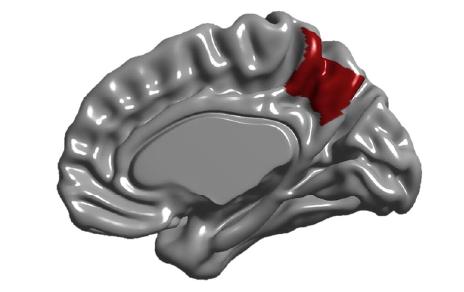

El precúneo se sitúa en la hendidura entre los dos hemisferios cerebrales. En la imagen resaltado en rojo sobre la cara interna de uno de los hemisferios. / E. Bruner.

Un estudio liderado por Emiliano Bruner, investigador del Museo Nacional de Ciencias Naturales (MNCN-CSIC), demuestra que el precúneo, una región estratégica del cerebro encargada de la consciencia de uno mismo, la percepción corporal, la memoria autobiográfica y la construcción de la identidad alcanza sus proporciones y forma casi definitivas antes de los tres años. Las diferencias individuales en esta zona, muy pronunciadas entre adultos, ya se aprecian después del parto, lo que apunta a que las provocan factores genéticos o prenatales.

Esta es la primera vez que se hace un estudio del desarrollo desde el nacimiento hasta la edad adulta de esta región del cerebro, una pieza central en la red cerebral humana que se halla escondida en el espacio entre los dos hemisferios cerebrales. El trabajo, publicado en la revista Cerebral Cortex, demuestra también que las regiones inferior y superior del precúneo crecen de manera independiente, por lo que no deberían estudiarse en conjunto, como a menudo se hace en la actualidad.

“Situado entre los dos hemisferios cerebrales, es una región clave para procesos complejos como la imaginación, la consciencia y la construcción del yo. La parte superior integra información somática y visual para situar el cuerpo en un marco espacial, mientras que la inferior conecta esta información con la memoria episódica de experiencias personales”, contextualiza el primer autor del estudio, Emiliano Bruner. “Ambas zonas se distinguen porque tienen funciones y cableado diferentes, por eso es tan importante estudiarlas de manera independiente ya que implican procesos distintos”, resalta este experto.